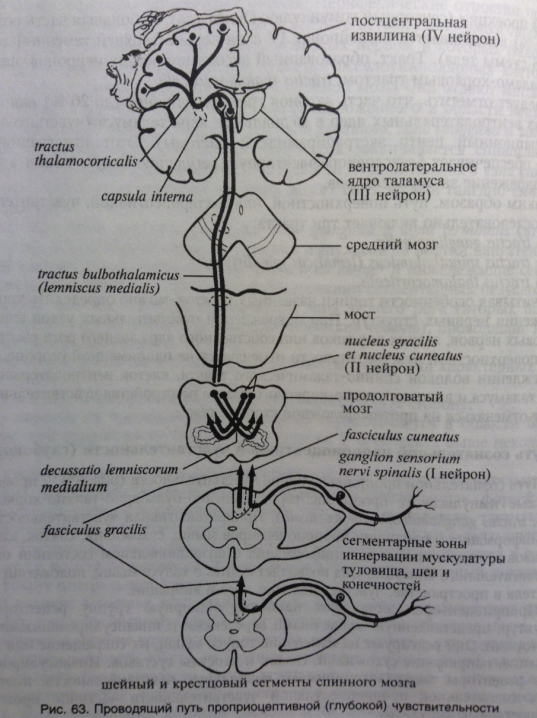

Пирамидная симптоматика в неврологии: ключевые аспекты